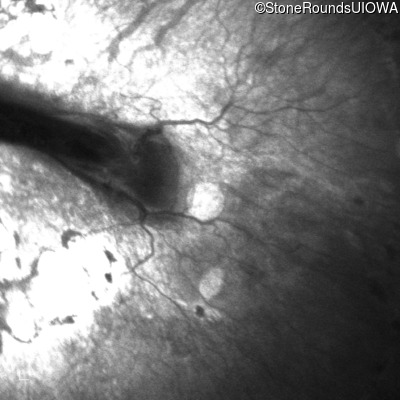

Infrared Fundus Photograph - Right - 10/200

Exemplar